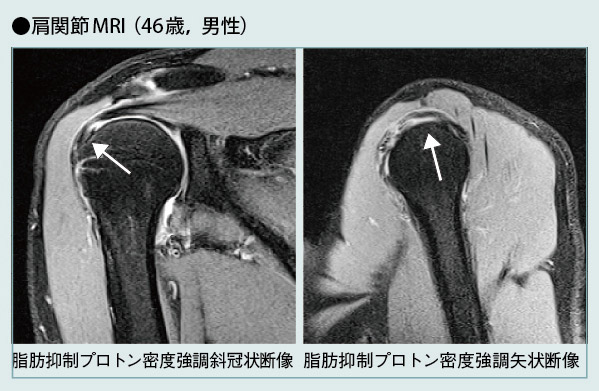

棘上筋腱の断裂が明瞭に描出されている。

MAGNETOM Verioについて,同院では,特に70cmオープンボアを高く評価している。中村美穂技師は,その有用性について,「MRIで優れた脂肪抑制画像を得るためには,磁場の中心に撮像部位をポジショニングする必要がありますが,これまではボアが狭いため,肩や関節などは困難でした。しかし,MAGNETOM Verioでは,それが可能となりましたので,これまでに経験したことのない高画質の脂肪抑制画像が得られています」と述べている。また,膝を立てたり,横向きになったりして,楽な姿勢で検査を行うことが可能となったため,撮像時の患者さんの苦痛が大幅に軽減されたのはもとより,安静を保ちやすいことが画質の向上にもつながっている。撮像時の圧迫感も大幅に軽減され,閉所恐怖症の患者さんでも,いまのところ,